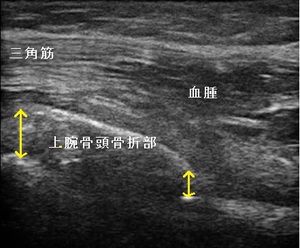

左肩レントゲン正面像 左上腕骨骨頭部 超音波長軸像

左腕を固定しているので首や肩、背中がいたくなり、当接骨院へ来院されました。骨折部を超音波観察したところ、

転位が約1cmと離解していた為、骨癒合後は左肩の関節可動域制限が起こることが予想されました。(右上画像の

矢印)